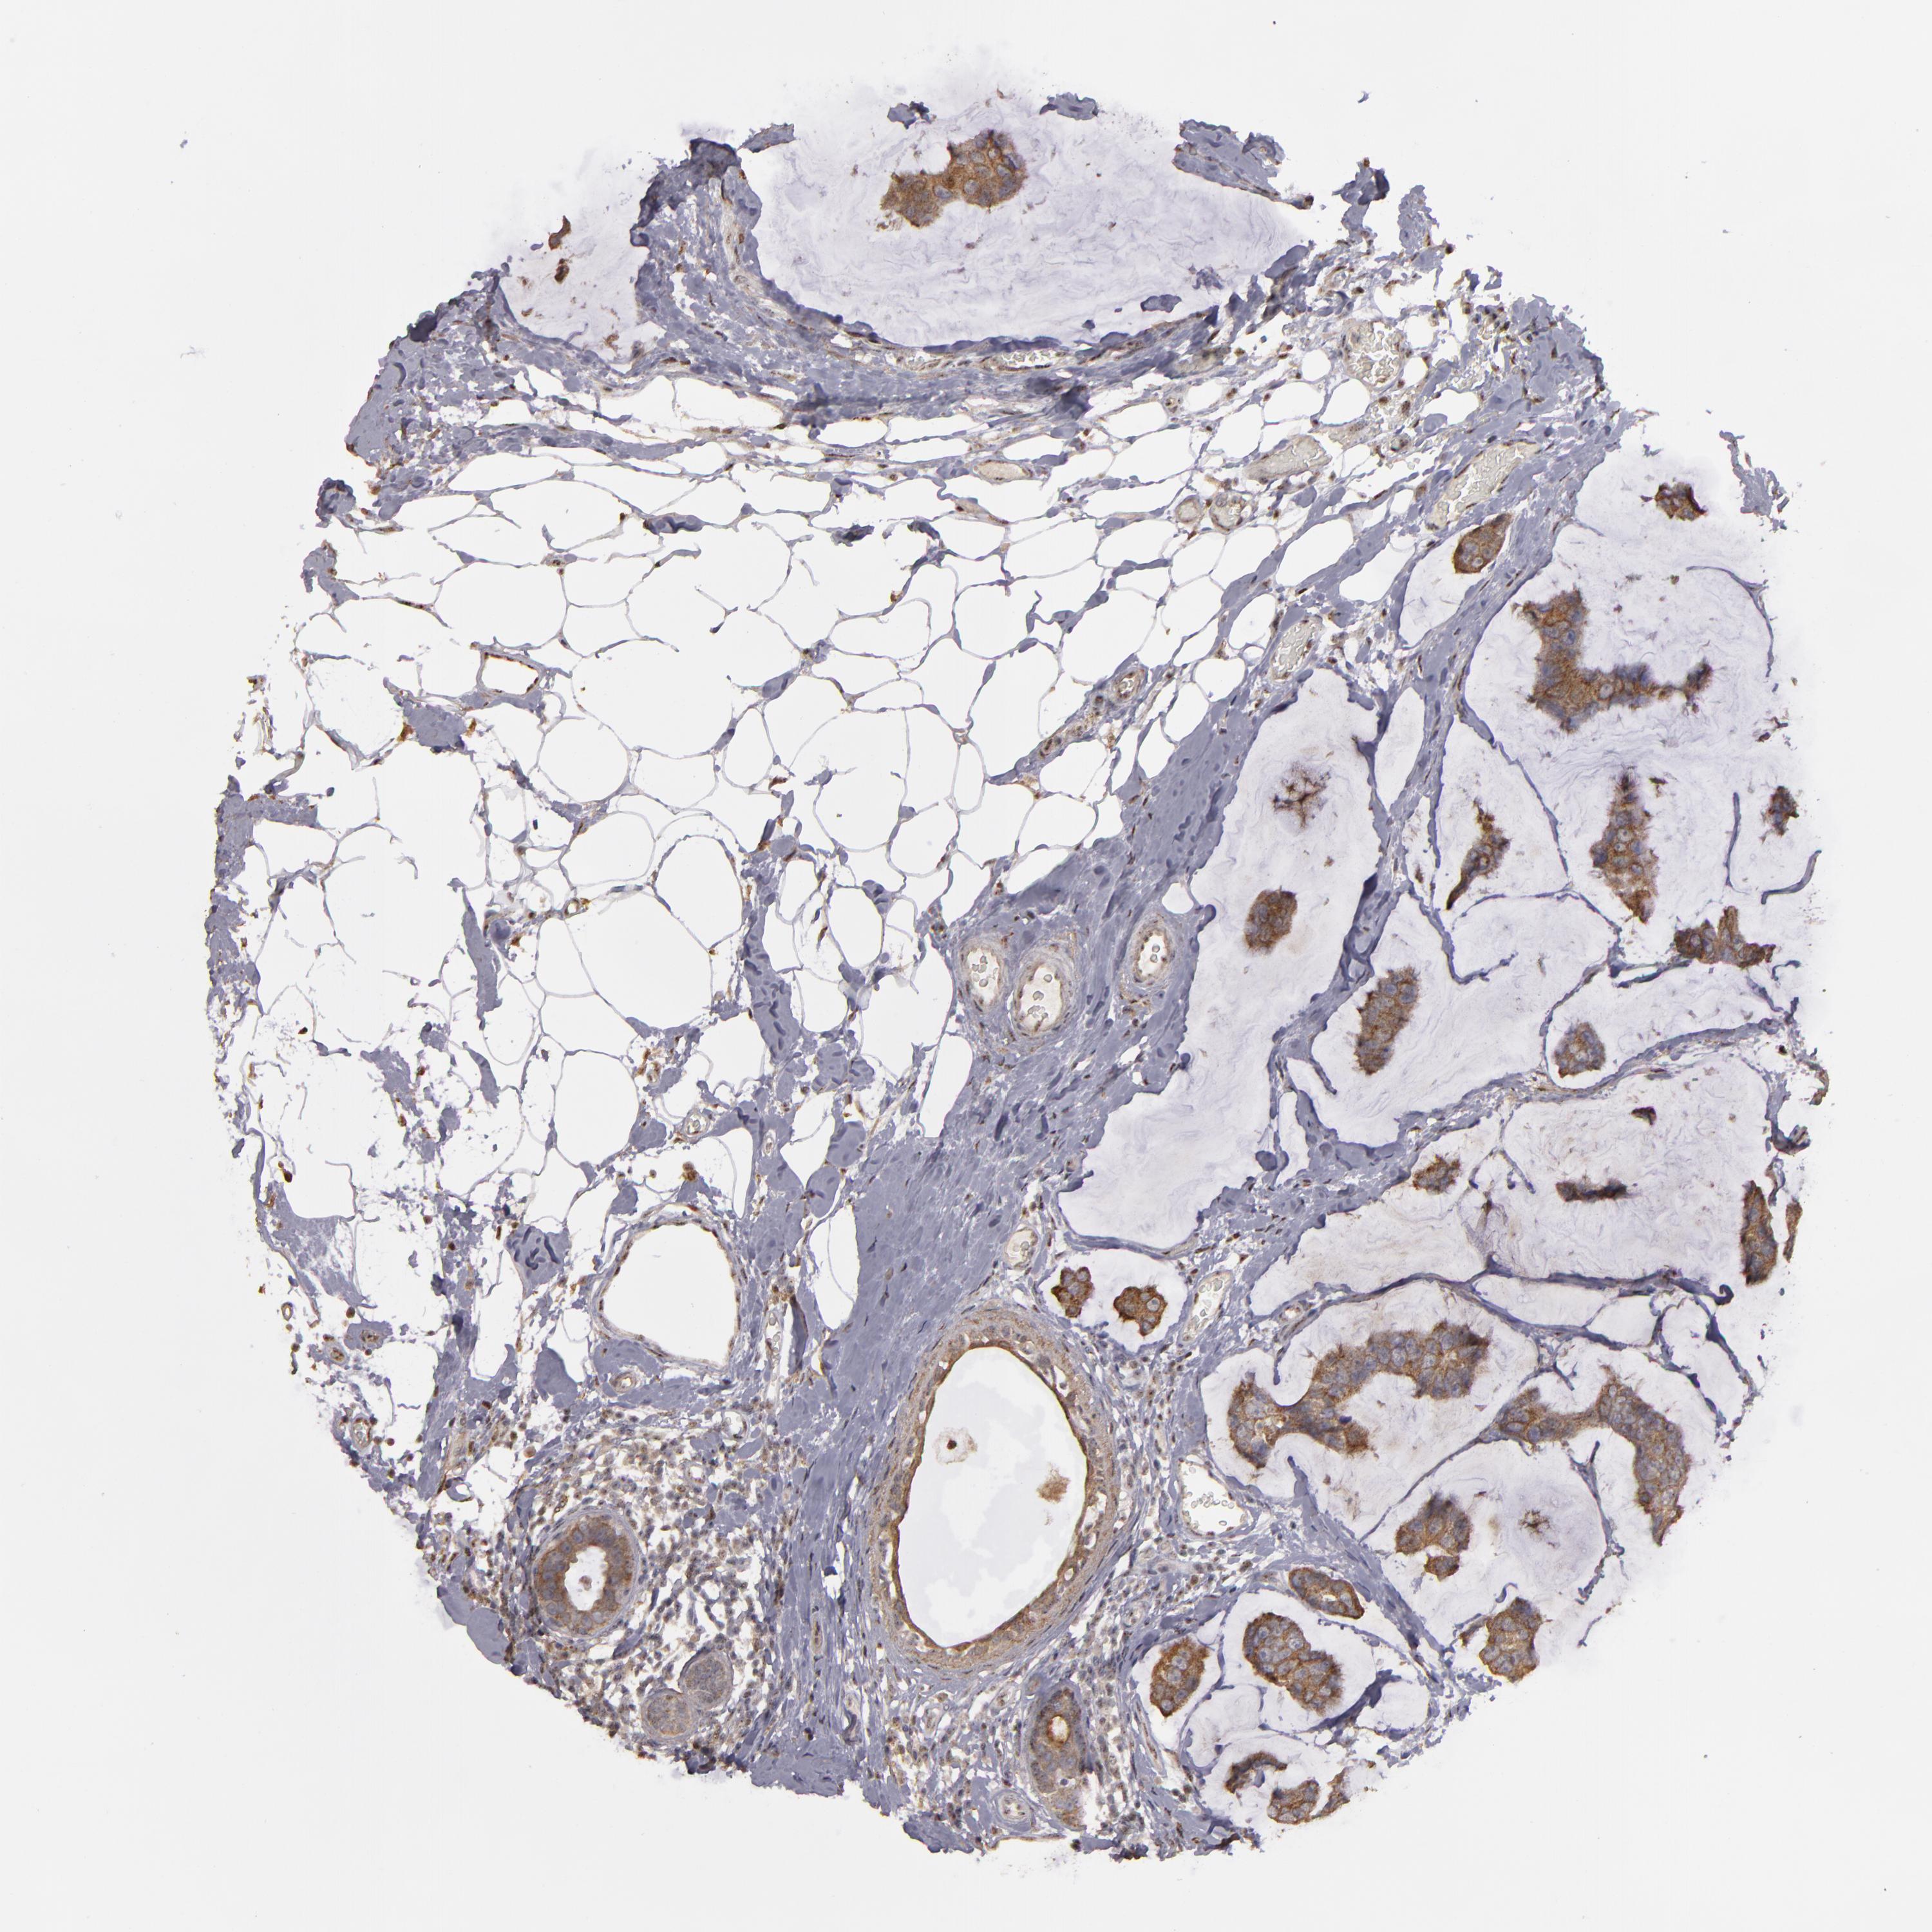

CANCER BREAST CANCER Show tissue menu

BRCA TCGA BRCA VALIDATION PROTEIN EXPRESSION